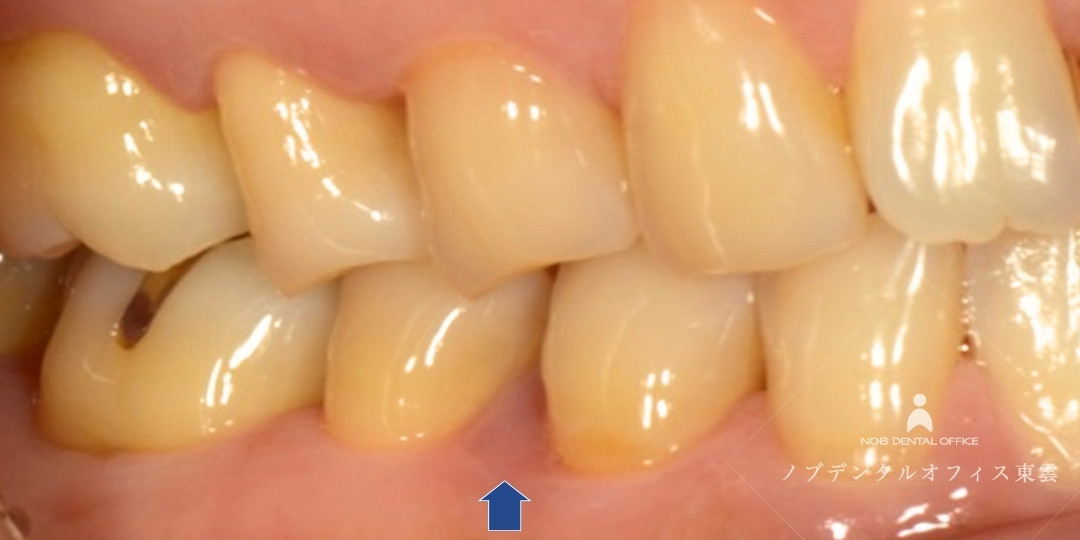

治療後は、歯ぐきの状態が安定し、約半年後のレントゲンで骨の回復傾向が確認されました。

奥歯については、噛み合わせや清掃性も考慮し、この後、セラミックインレーで修復を行います。

歯ぐきがひきしまり、しっかり歯をおおっています。この後セラミック治療を行いました。